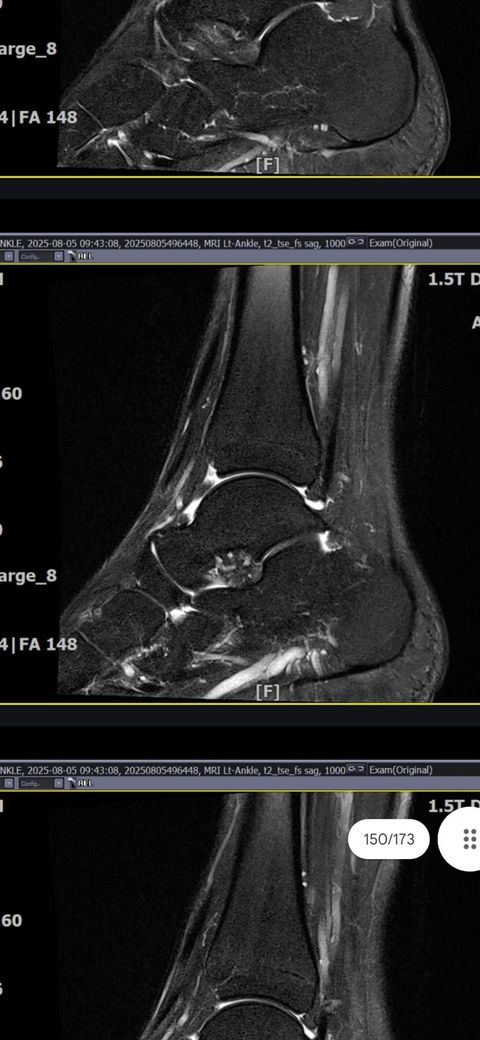

그래도 통증이 남아 8월 5일에 MRI를 촬영했는데, 병원에서는 “인대는 이어져 있고, 이 정도면 재활운동으로 호전될 것”이라는 설명을 들었습니다.

MRI 상 전거비인대와 발목 상태가 정말 회복 단계인지, 아니면 만성으로 넘어가는 건 아닌지 전문가분들의

의견을 듣고 싶습니다.

올려주신 mri를 보면 전거비인대는 연속성이 유지되고 있고 파열이나 큰 손상 흔적은 없어 재활로 회복 가능한 상태로 보입니다 다만 3개월 가까이 활동 시 통증과 미열감이 남아 있는 것은 조직 회복이 아직 완전히 끝나지 않았거나 주변 연부조직 관절 움직임 제한 등으로 인한 과민 반응일 수 있습니다.

초음파와 비교하면 mri 상으로 인대 연속성이 확인되므로 심각한 악화나 재파열은 아닌 것으로 판단됩니다

MRI상에서는 인대의 회복이 이루어지고 있는 덧으로 보이지만 인대의 회복은 소요되는 시간이 오래 걸리고, 주변 근육의 약화나 기능 저하로 인해 통증이나 불편감이 지속될 수 있습니다.